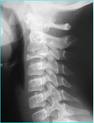

L’ostéopathe sera amené à demander au patient des examens complémentaires comme des radiographies, IRM, scanners, pour une meilleure prise en charge du patient.

• Les Cervicalgies Traumatiques : Les douleurs de la région du cou peuvent apparaître à la suite d’un accident de voiture (whiplash) ou d’une chute importante sur la tête ou le coccyx. Même si les examens complémentaires comme la radiographie n’ont rien montré, certaines structures peuvent être en souffrance d’un point de vue ostéopathique .Le travail de l‘ostéopathe consistera à diminuer ou éliminer ces souffrances.